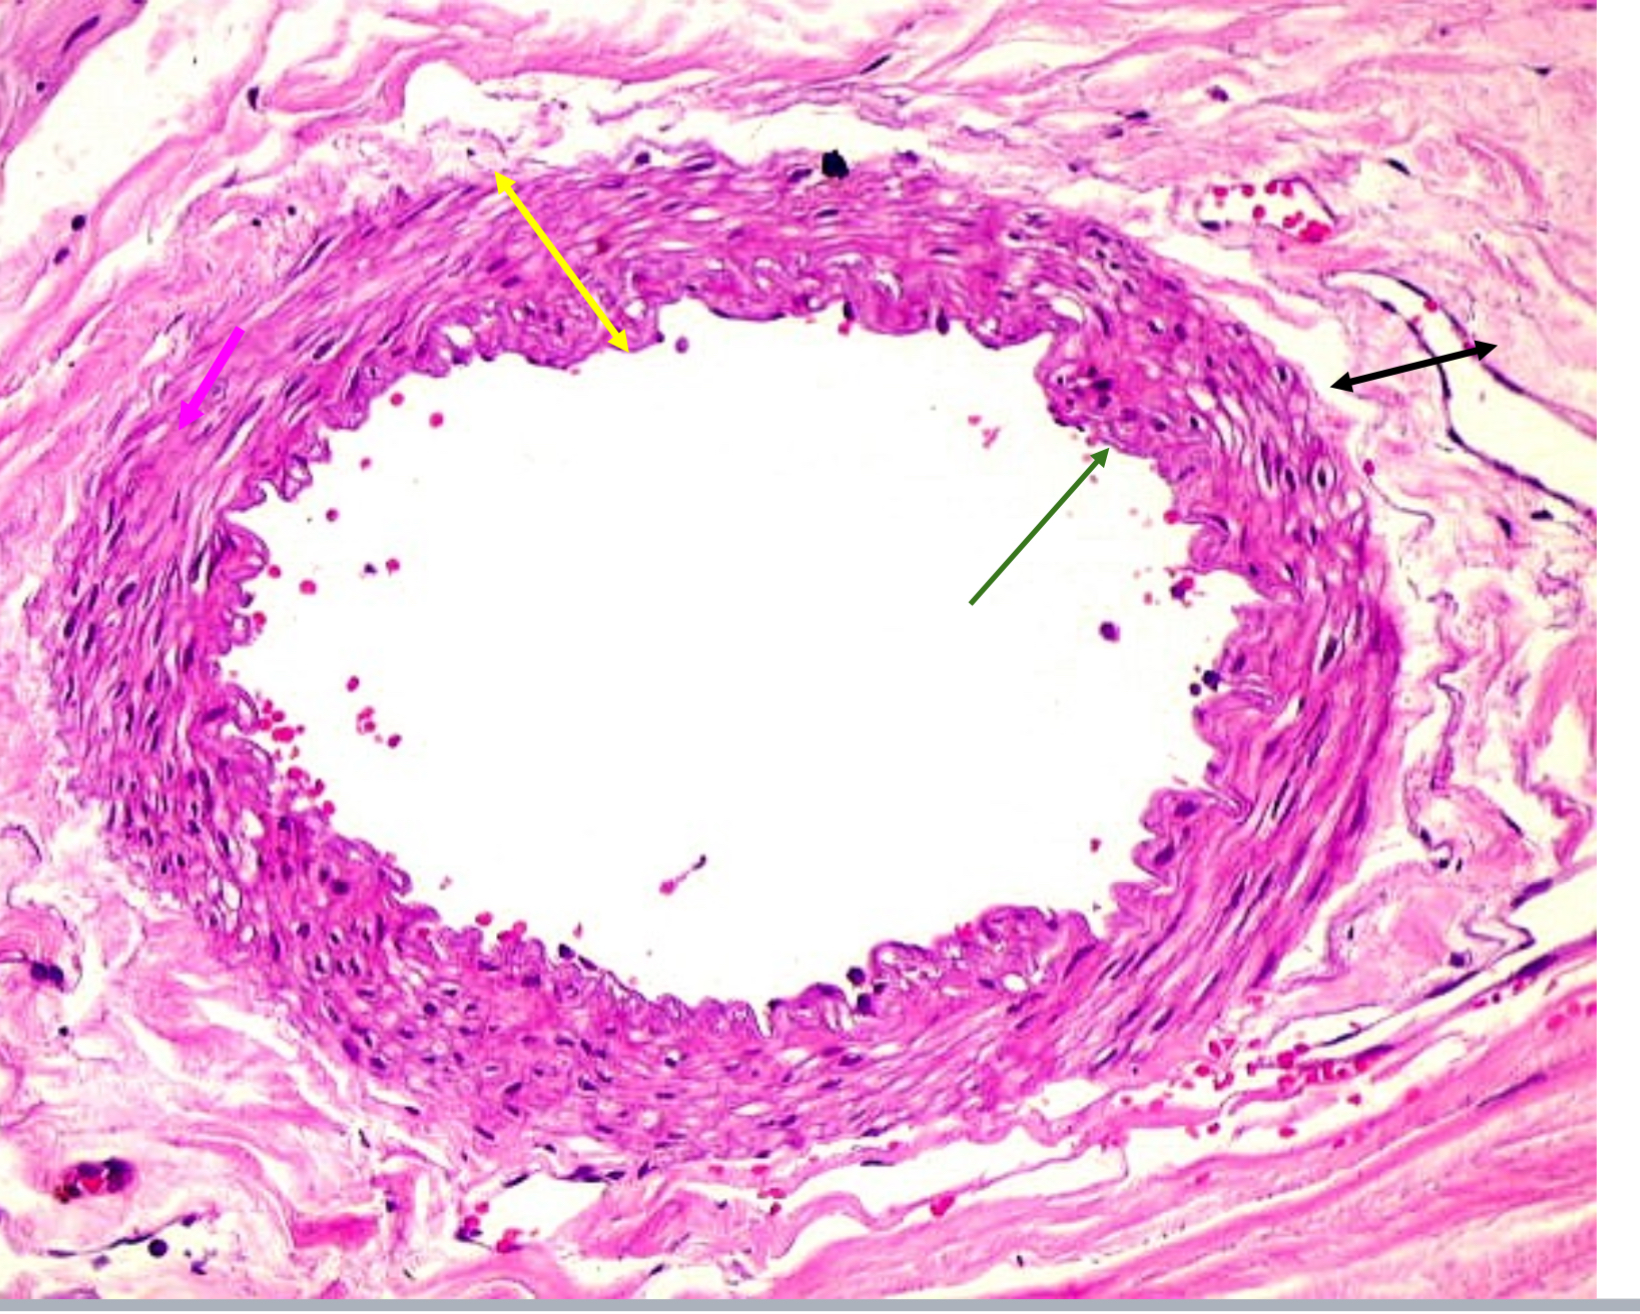

Tunica intima

Name the blue arrow

Lines lumen and release vasoactive chemicals

Function of tunica intima

Tunica media

Name green arrow

Vasoconstriction and vasodilation

Function of tunica media

Tunica externa

Name the purple arrow

Anchor and bind vessel

Function of tunica externa

Artery

Artery or vein?

Tunica intima

Name the green arrow

Tunica media

Name the yellow

Tunica externa

Name the black